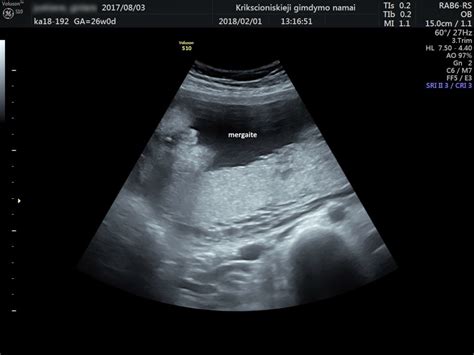

Amniocentezė atliekama įvedant adatą per motinos pilvo sieną ir gimdą į amniono ertmę, kurioje vaisius yra apsuptas vaisiaus vandenimis. Šiuo metu išsiurbiama nuo 15 iki 20 kubinių centimetrų vaisiaus vandenų. Šis tyrimas paprastai atliekamas tarp 16-os ir 18-os nėštumo savaitės.